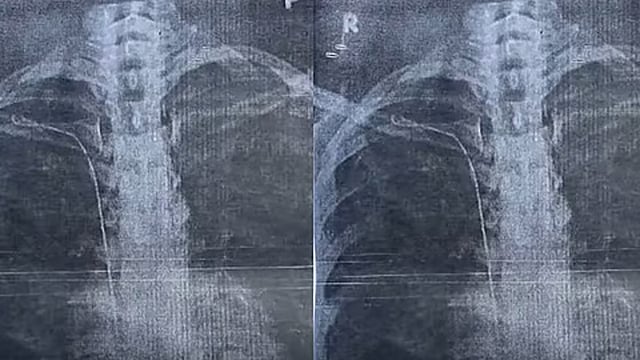

തിരുവനന്തപുരം: ഇരുപത്തിയാറുകാരിയുടെ ജീവിതം വഴിമുട്ടിച്ച് തിരുവനന്തപുരം ജനറൽ ആശുപത്രിയിലെ ഗുരുതര ചികിത്സാ പിഴവ്. തൈറോയ്ഡ് ഗ്രന്ഥി നീക്കം ചെയ്യാനുള്ള ശസ്ത്രക്രിയക്കിടെ 50 സെന്‍റീ മീറ്റർ നീളമുള്ള സർജിക്കൽ ട്യൂബ് യുവതിയുടെ നെഞ്ചിൽ കുടുങ്ങി. കാട്ടാക്കട സ്വദേശി സുമയ്യയുടെ നെഞ്ചിലാണ് സർജറിക്കിടെ ട്യൂബ് കുടുങ്ങിയിരിക്കുന്നത്.

ഇതുസംബന്ധിച്ച് ജനറൽ ആശുപത്രിയിലെ ഡോക്റ്റർ രാജീവ്‌ കുമാറിനെതിരേ യുവതി പരാതി നൽകിയിട്ടുണ്ട്. 2023 മാർച്ച്‌ 22നാണ് യുവതി സർജറിക്ക് വിധേയയായത്. ആരോഗ്യ പ്രശ്നം ഉണ്ടായപ്പോൾ ഇതേ ഡോക്റ്റർക്ക് കീഴിൽ രണ്ടു വർഷം ചികിത്സ തുടർന്നു. ആരോഗ്യപ്രശ്നം കടുത്തപ്പോൾ മറ്റൊരു ആശുപത്രിയിൽ ചികിത്സ തേടി. എക്സ്റേയിലാണ് നെഞ്ചിനകത്ത് ട്യൂബ് കണ്ടത്.

വീണ്ടും സന്ദർശിച്ചപ്പോൾ ഡോക്റ്റർ പിഴവ് സമ്മതിച്ചെന്ന് യുവതി പറഞ്ഞു. മറ്റു ഡോക്റ്റർമാരുമായി സംസാരിച്ച രാജീവ്‌ കുമാർ കീ ഹോൾ സർജറിയിലൂടെ ട്യൂബ് പുറത്തെടുക്കാമെന്ന് യുവതിയെ അറിയിക്കുകയും ചെയ്തു.

സംഭവം രഹസ്യമാക്കിവയ്ക്കണമെന്ന് ഡോക്റ്റർ ആവശ്യപ്പെട്ടതായും യുവതി വെളിപ്പെടുത്തി. പിന്നീട് രാജീവ്‌ കുമാറിന്‍റെ നിർദേശപ്രകാരം ശ്രീചിത്ര ആശുപത്രിയിൽ ചികിത്സ തേടി. രക്തക്കുഴലുമായി ട്യൂബ് ഒട്ടിച്ചേർന്നെന്ന് സിടി സ്കാനിൽ വ്യക്തമായി.